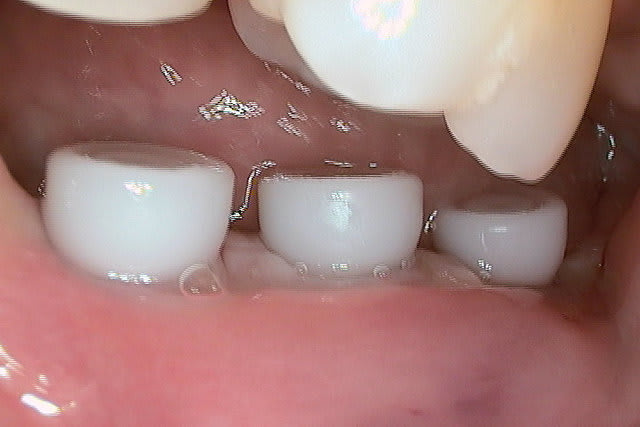

une fin cas en passant. 7 semaines après implantation.Je n'ai pas les photos du début du cas ici mais si cela intéresse quelques uns je peux les mettre en rentrant.

le dernière photo c'est 8 semaines après les autres le jour de l'implantation.